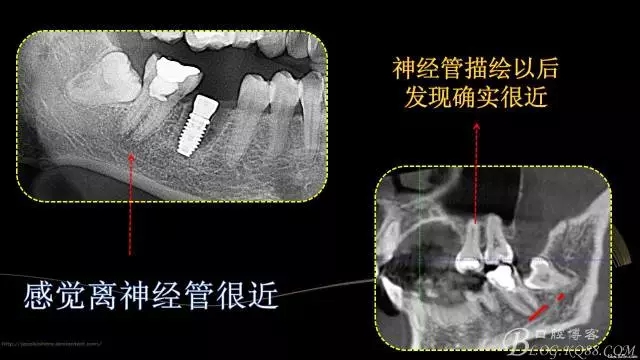

行走在神經(jīng)管上的根管治療